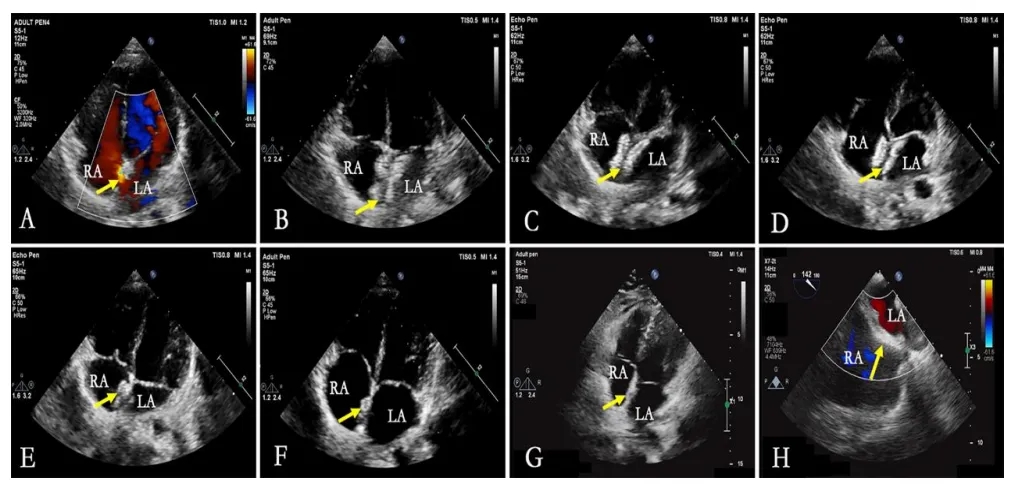

e图7. 生物可降解封堵器24个月随访期间形态变化的超声心动图评估 (RA-右心房,LA-左心房)

A. 术前评估显示房间隔缺损(箭头指示)

B-G. 分别为出院前及术后1、3、6、12、24个月时的经胸超声心动图四腔心切面,显示封堵器形态(箭头指示)

H. 24个月时经食道超声心动图显示封堵器降解后房间隔形态(箭头指示)